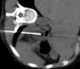

Functioning adrenal adenoma

Adrenocortical adenoma is commonly described as a benign neoplasm emerging from the cells that comprise the adrenal cortex. Like most adenomas, the adrenocortical adenoma is considered a benign tumor since the majority of them are non-functioning and asymptomatic. [Source: Wikipedia ]